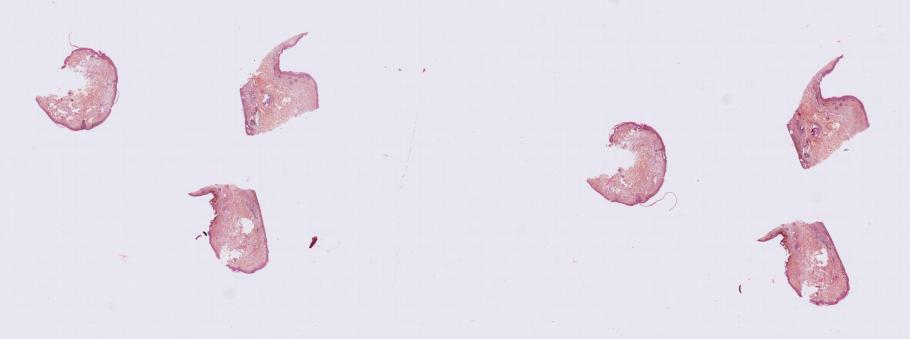

Une base de données unique de lames histologiques de mélanome

Plus de 25 centres hospitaliers et 40 laboratoires francophones d'anatomie pathologique ont participé à la constitution d'une base de données de près de 2 000 patients. Cette base est composée d’images de lames histologiques d'exérèse de mélanome annotées par des experts et associées à des données cliniques issues de la base de données nationale du Réseau national pour la Recherche et l'Investigation Clinique sur le Mélanome (RIC-Mel).